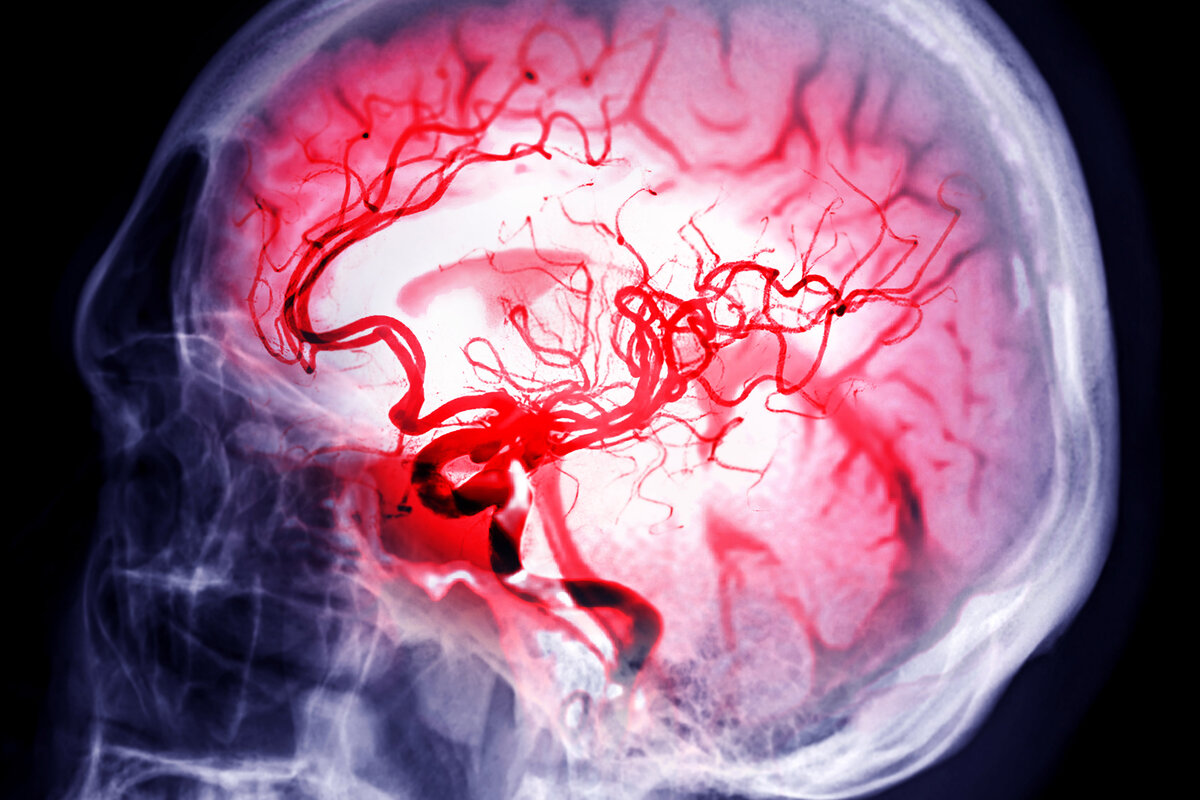

L’attaque cérébrale ou accident vasculaire cérébral (AVC) frappe toutes les 30 minutes en Suisse et affecte une personne sur quatre au cours de sa vie. Un quart des victimes en meurt et un tiers reste handicapé.

Jusqu’à 90 % des AVC sont évitables ! Une série de 10 facteurs de risque, modifiables, augmentent la probabilité de développer un AVC : hypertension artérielle, tabagisme, diabète, hypercholestérolémie, régime alimentaire déséquilibré, manque d’activité physique, excès pondéral, excès d’alcool, fibrillation auriculaire, stress et dépression.